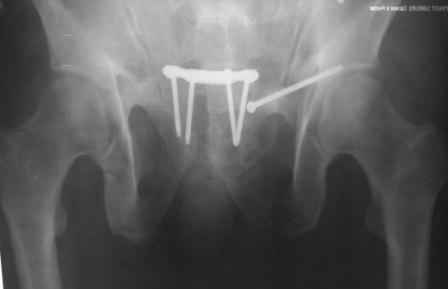

Уважаемые коллеги! спасбио Вам за советы и наставления! Рукводство получил, шикарно, отдельно спасбио А.Н.! Пациента сегодня активизировали, спокойно ходить с полной опорной нагрузкой. С уважением Ерсин Жунусов.

доступ.jpg

73KB (75258 bytes)

X-ray!

x-ray.jpg

33KB (34105 bytes)